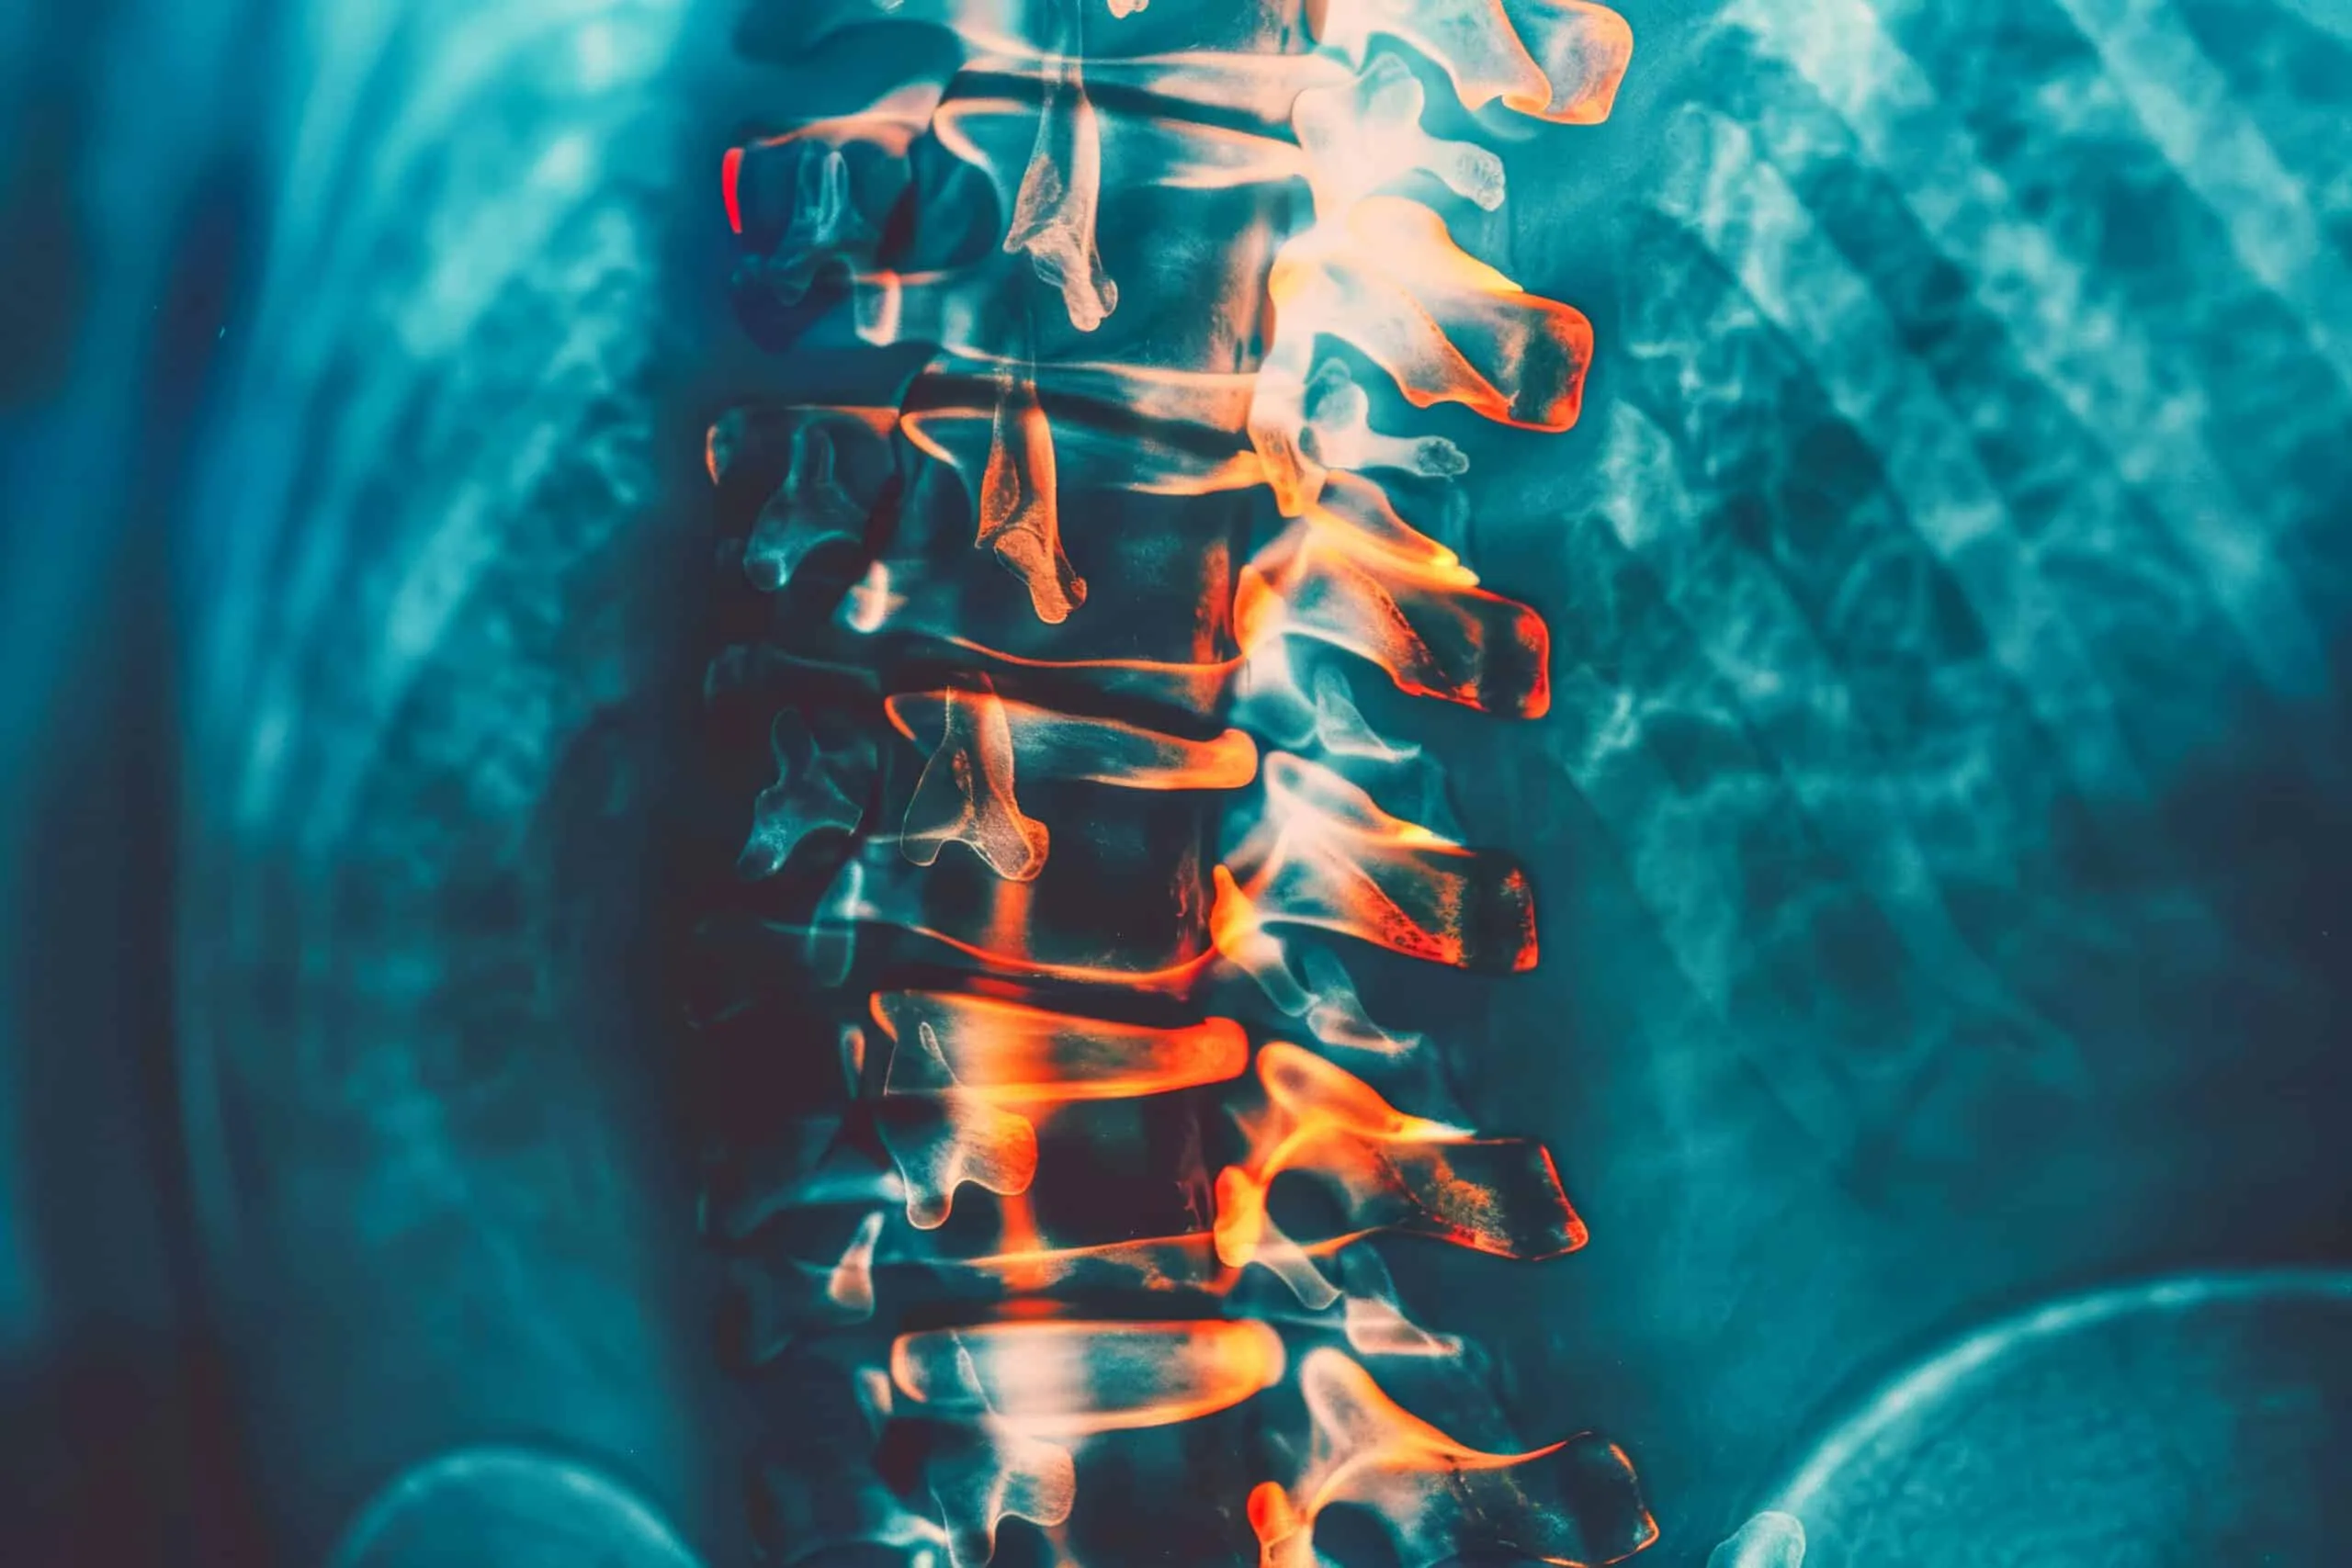

Spinal Cord Injury and Medical Cannabis

Spinal cord (SC), a tubular structure of nervous tissue, connects the brain to the peripheral nervous system. It conducts nerve...